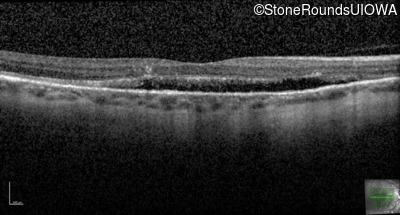

Optical Coherence Tomography - Left - 20/30 -2 sc

Exemplar / OCT Stack